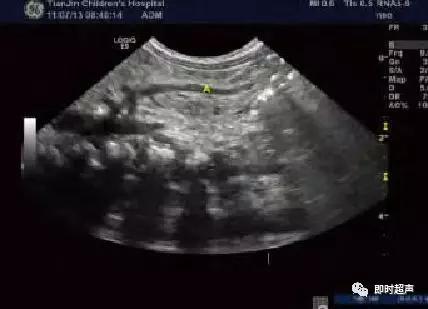

第一步 (一步扫查法):常规扫查观察有无扩张肠

管、增厚肠壁,有无Whirlpool征。同时于剑突下横切面平移探头观察SMA及SMV主干位置关系,判定有无位置逆转,这一步是目前大多数学者采用的扫查方法。

肠系 膜 上 血 管 根 部 呈 现SMV/SMA位 置 逆 转, 即SMV位于SMA左侧

第二步 (两步扫查法):重点进行肠系膜血管走行的扫查。在第一步的基础上探头顺时针旋转180°、配合患儿呼吸适度加压,并实时左右侧动探头,必要时做轻微的角度调整,清晰显示SMA和SMV主干血管直至纤细的末端 ,同时尽可能显示其主要分支,观察其走行情况。

SMV根部起始直至纤细的末端,“V”为SMV

SMA自AO发出直至纤细的末端,“A”为SMA

SMV连同所属的肠系膜和肠管围绕SMA发生顺时针旋转,超声横切面下呈现类似风暴引起的 “漩涡”征象

肠系膜动静脉位置异常,彩色血流漩涡征

肠系膜上动、静脉位置关系异常:AO IVC

CDFI:SMV围绕SMA旋转

肠扭转:肠系膜根部非均质低回声团

CDFI: 靶环征 螺旋状